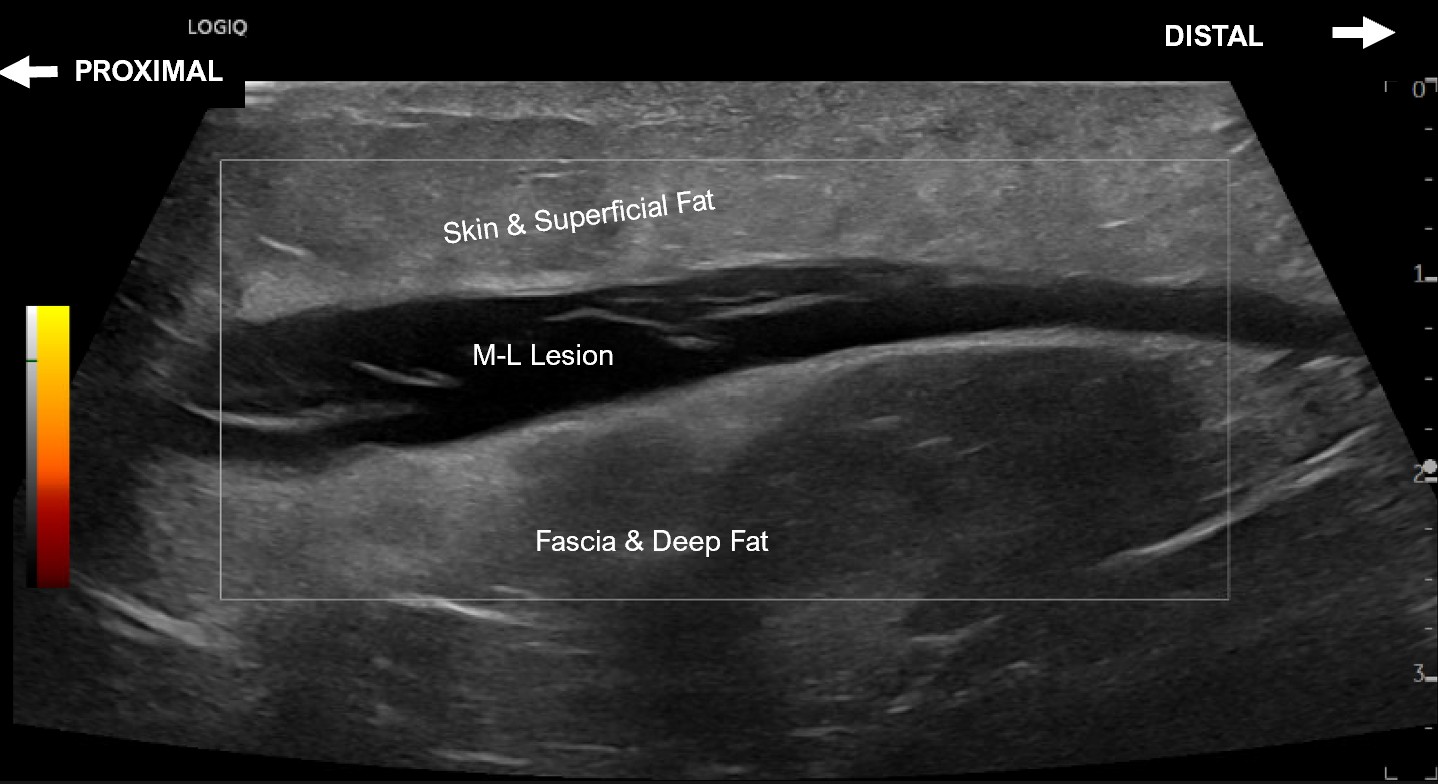

Labeled long axis view of a Morel-Lavallee lesion measuring with no evidence of flow on power doppler.

Labeled short axis extended view of the medial distal thigh and knee with evidence of a Morel-Lavallee lesion between the skin and superficial fat and the fascia and deep fat measuring approximately 10.5 cm from anterior to posterior.

Labeled long axis extended view of the medial distal thigh and knee with evidence of a Morel-Lavallee lesion between the skin and superficial fat and the fascia and deep fat measuring approximately 14.7 cm from proximal to distal.